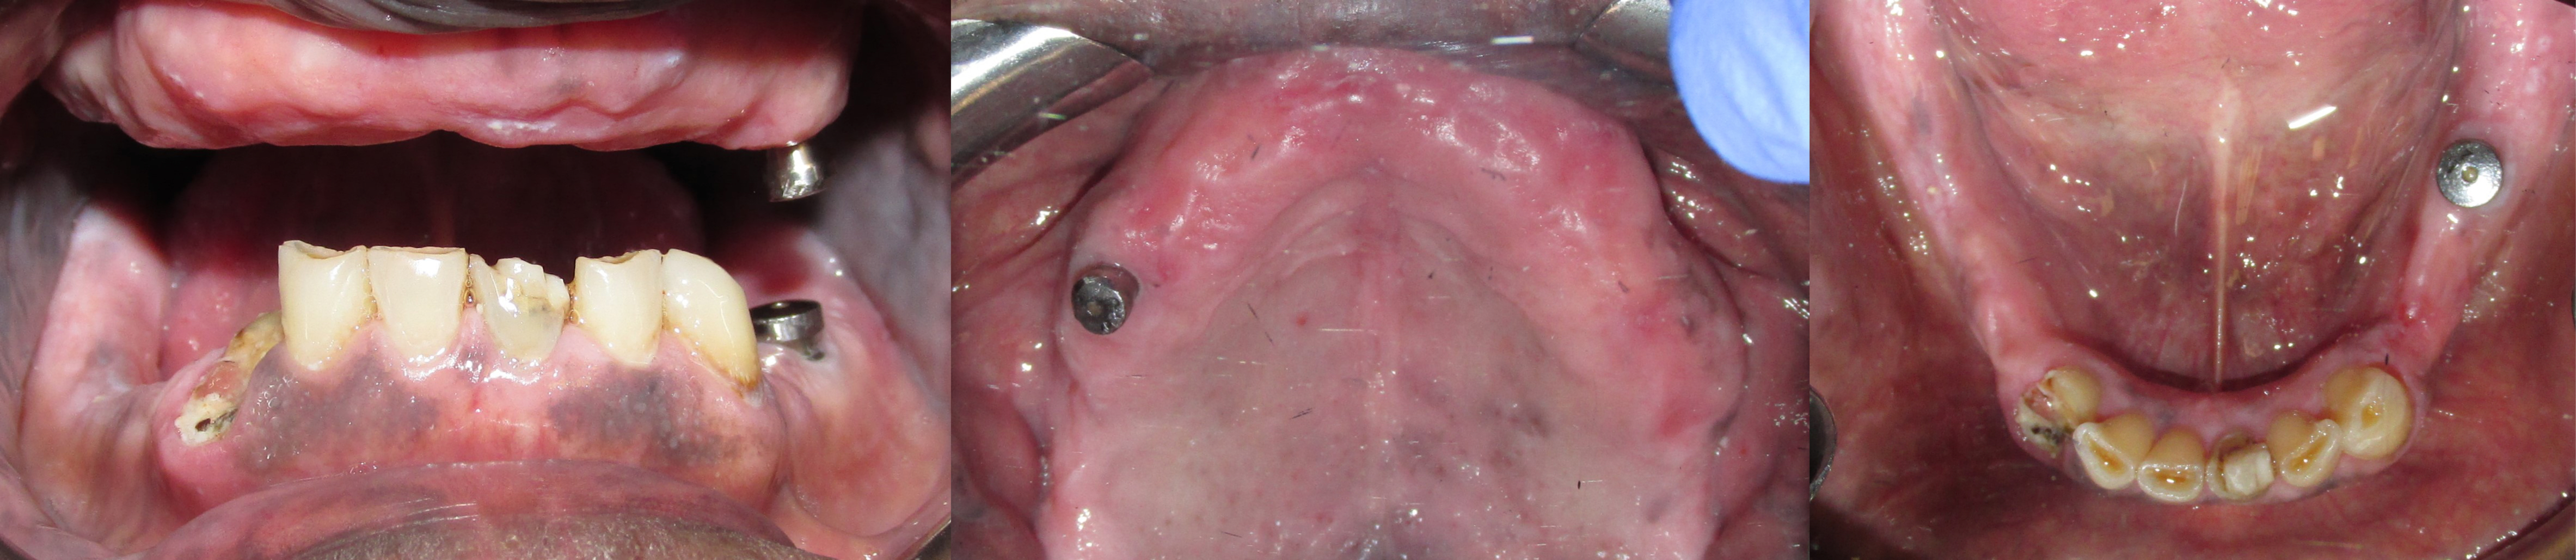

Dr. Glen Justice recently treated a male patient who was missing almost all of his teeth, had failing implants on his upper right and lower right premolars and had advanced periodontal disease on his lower incisors and canines. The patient complained that his current intra-oral condition was greatly affecting his functional ability, in addition to the resulting impact on his smile. The patient was urged to receive treatment to regain his mouths overall function to smile and eat comfortably.

Figure 1 shows the pre-treatment intraoral condition of the upper and lower teeth